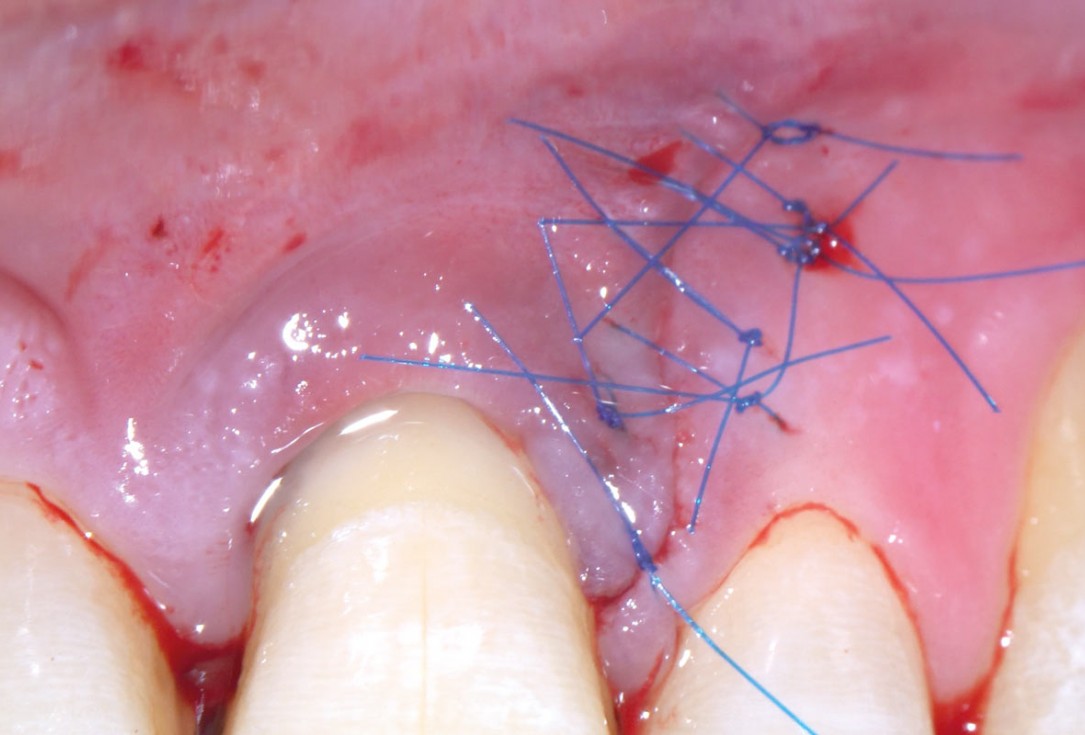

07/11 - Application of the membrane to cover the defect, stabilised with suturesEntire papilla preservation technique (EPP) for the regenerative treatment of a severely compromised central incisor - Dr. S. Aslan

08/11 - Primary wound closure with microsurgical suturing techniqueEntire papilla preservation technique (EPP) for the regenerative treatment of a severely compromised central incisor - Dr. S. Aslan